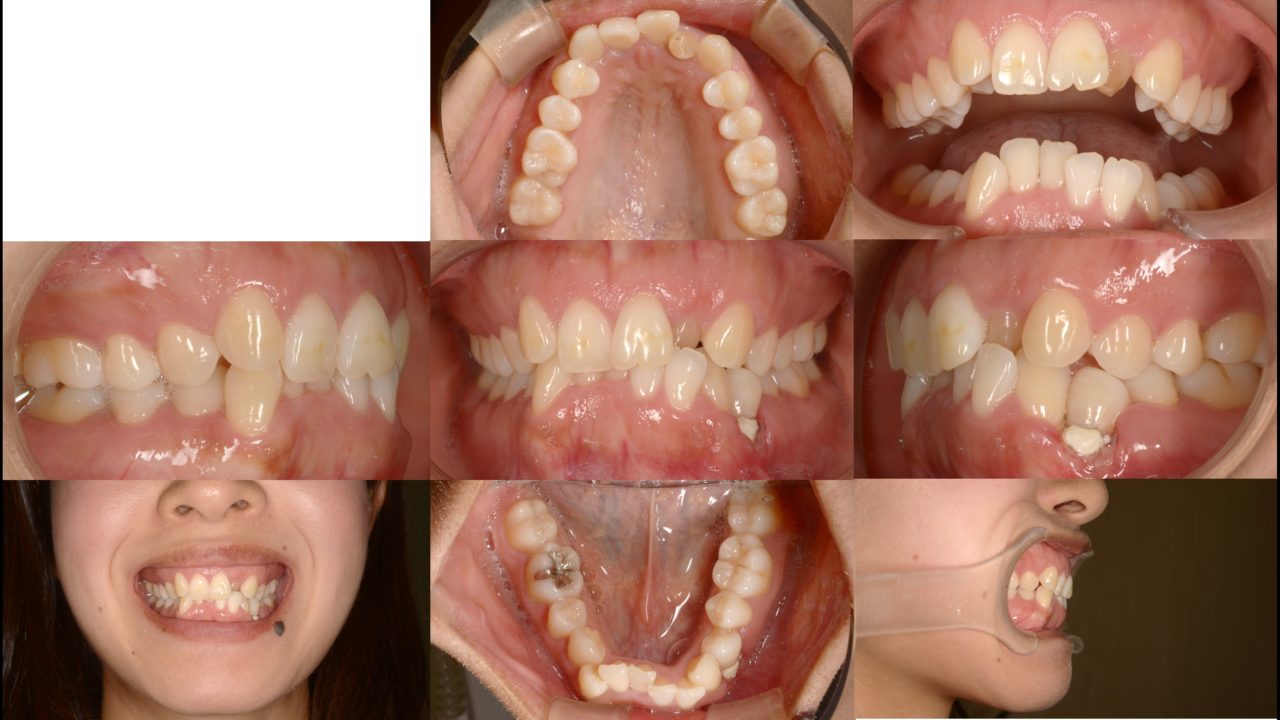

Before

| 主訴 | 前歯の歯並びを治したい |

| 診断 | 左側アングルクラスⅠ 右側アングルクラスⅡ |

| 矯正方法 | 2本抜歯を伴うマルチブラケットシステム |

| 矯正期間 | 26か月 |

| 費用 | 730,000円(税別) |

| 調整料 | 5,000円(税別) |

| 備考 | 前歯の凸凹が気になるとのことでした。旦那さんも当院で矯正治療を受けていたので、奥さんもついでに治すことになりました。左上側切歯は失活しており、変色が目立つ状態でした。また、左下第1小臼歯は歯頚部に大きなむし歯があり、歯肉退縮が著しい状態でした。叢生を解消するために抜歯が必要だったので、この状態の悪い2本と右下第1小臼歯の全部で3本を抜歯することにしました。治療後は口元の印象が劇的に良化しました。 |